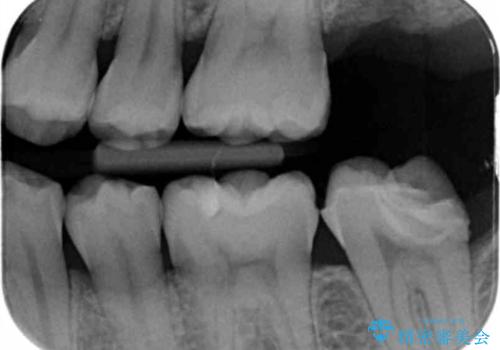

- 他院で入れたセラミックの詰め物が取れてしまい来院。

適合を確認したところ、不適合だったため新しく形を作り直して、型取りをした方が良いことを説明した。

セラミックの詰め物で治療すると、詰め物の範囲が大きくなり、割れてしまう可能性があるので以下の治療の提案をした。

二つの提案をしたところ、①を選択されたのでゴールドインレーによる治療を行いました。